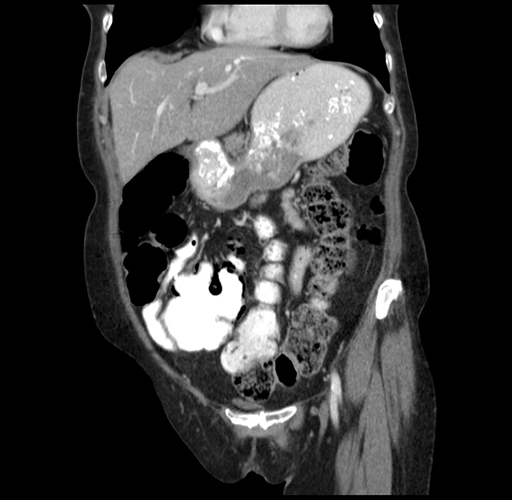

Pre-Chemo: Coronal Venous